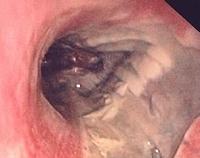

Deposition of fibrin